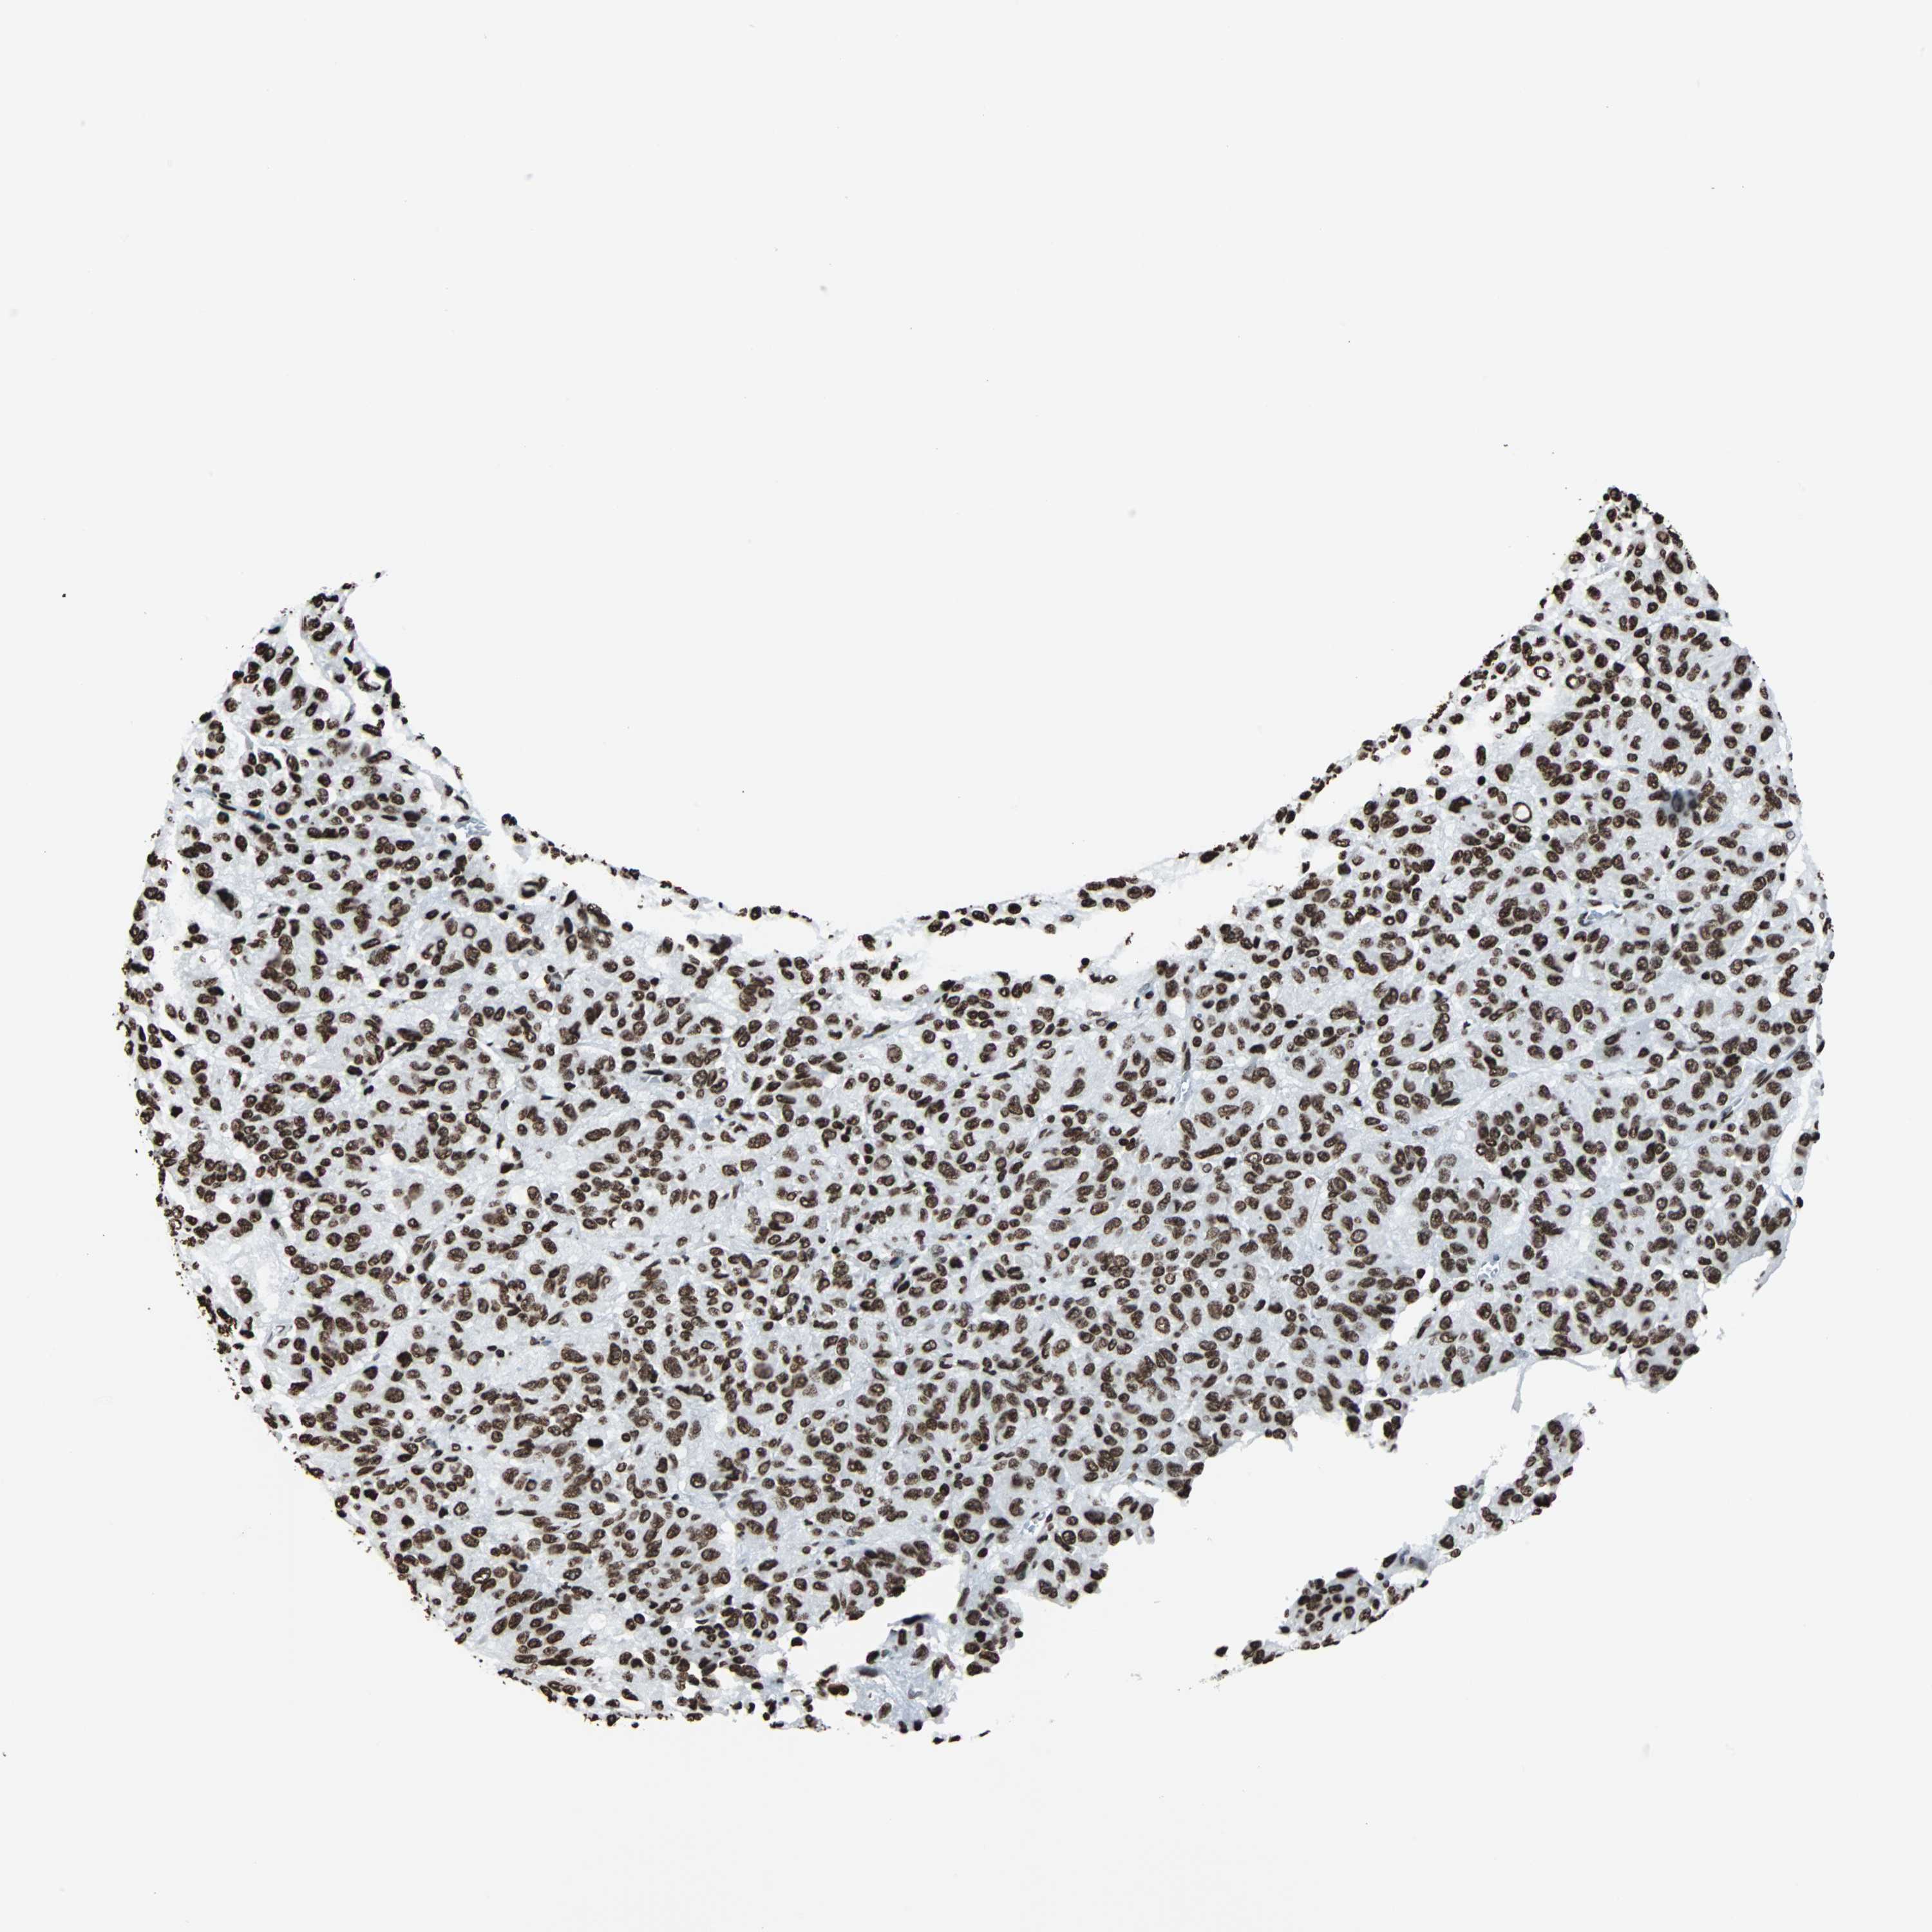

MELANOMA - Protein expressioni

A mouse-over function shows sample information and annotation data. Click on an image to view it in a full screen mode. Samples can be filtered based on level of antibody staining by selecting one or several of the following categories: high, medium, low and not detected. The assay and annotation is described here.

Note that samples used for immunohistochemistry by the Human Protein Atlas do not correspond to samples in the TCGA dataset.

Antibody stainingi

Antibody staining in the annotated cell types in the current human tissue is reported as not detected, low, medium, or high, based on conventional immunohistochemistry profiling in selected tissues. This score is based on the combination of the staining intensity and fraction of stained cells.

Each image is clickable and will lead to virtual microscopy that enables deeper exploration of all samples and also displays staining intensity scores, fraction scores and subcellular localization as well as patient and tissue information for each sample.

Antibody CAB007814

Staining

High

Intensity

Quantity

Location

Malignant melanoma, NOS

Malignant melanoma, Metastatic site